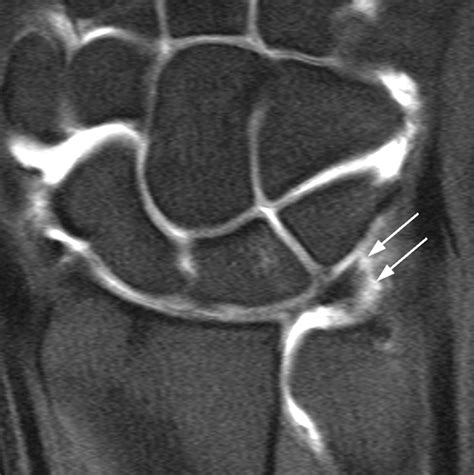

• Imaging Tests: X-rays, MRI, or CT scans may be ordered to visualize the knee joint and confirm the diagnosis. MRI is particularly useful for detecting soft tissue injuries like cartilage tears.